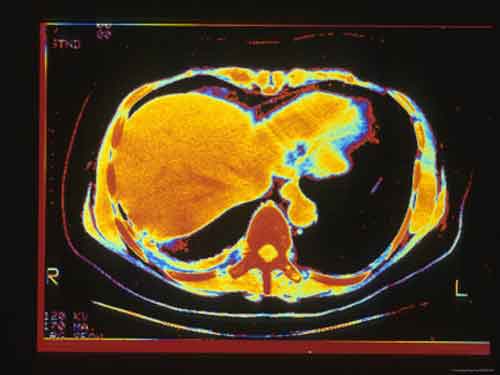

Trapianto di fegato: un modello matematico per stabilirne la necessità e salvare vite umane

Ricercatori dell’universita’ dello Utah hanno sviluppato un insieme di equazioni di calcolo che aiuta a comprendere se e in quali quantita’ i pazienti assumono il paracetamolo come antidolorifico e valutare se e’ necessario un trapianto di fegato per sopravvivere.